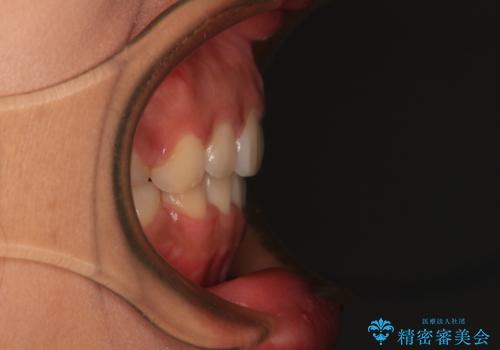

- 出っ歯と口の閉じにくさ、デコボコを気にして来院された患者様です。

口元の突出感を改善するため、上下左右第一小臼歯4本の抜歯を行い、ワイヤー装置による矯正治療を行うこととしました。

舌の突出癖により上下前歯は非接触であり、非常に前方に飛び出している状態でした。

舌のトレーニングをしっかりと行っていただき、口の閉じやすい歯並びに仕上げることができました。